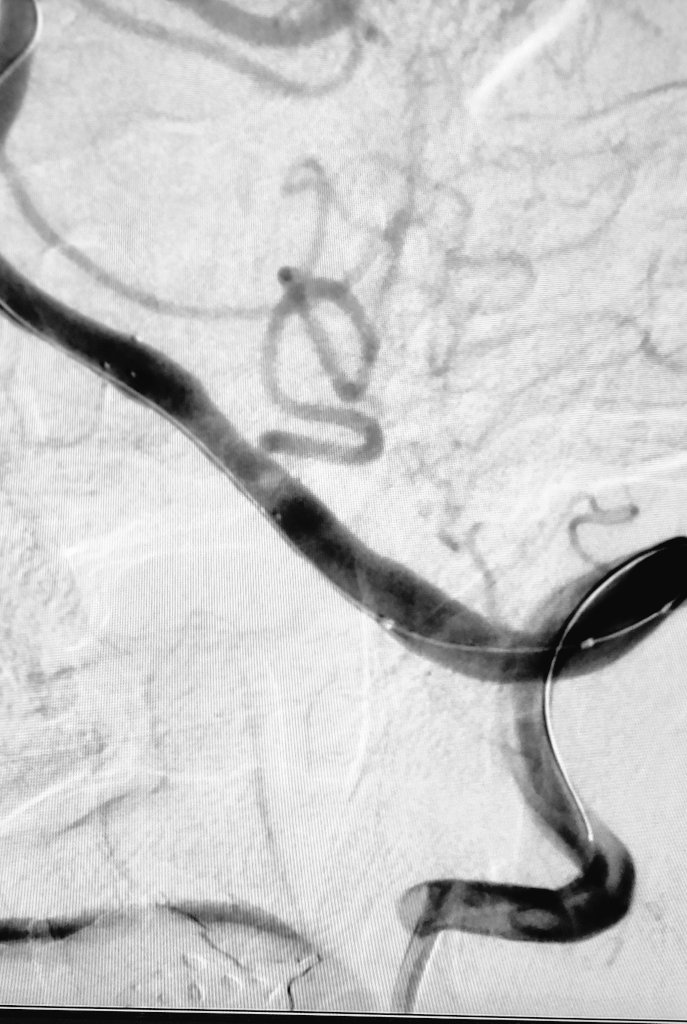

Trombectomía arteria cerebral media izq. Técnica: ARTS (Aspiration-Retriever Technique for Stroke). Tiempo de procedimiento: ⌛10 min Stent : StrykerNeurovascular Trevo 6x25mm Catéter de aspiración distal: AXS Catalyst™ 6

Trombectomía arteria cerebral media izq.

Técnica: ARTS (Aspiration-Retriever Technique for Stroke).

Tiempo de procedimiento: ⌛10 min

Stent : <a href="/Stryker_NV/">StrykerNeurovascular</a> Trevo 6x25mm

Catéter de aspiración distal: AXS Catalyst™ 6